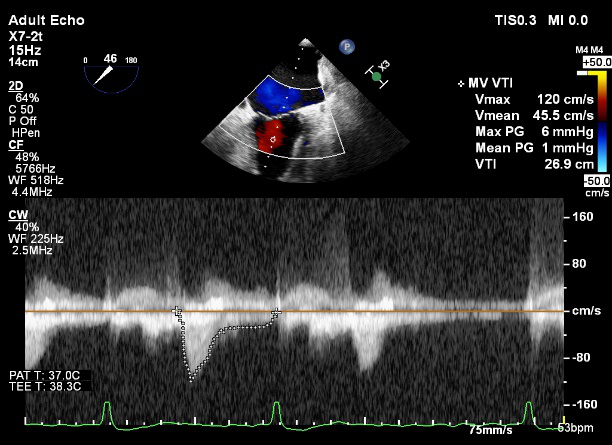

术前超声诊断

LVOT-color:MR(重度),返流面积11.3cm2

肺静脉血流频谱呈收缩期反向

3D-color MV view:血流主要来源于2、3区

Qlab软件勾画估测瓣口面积约:6.16cm2

TEE LVOT切面返流量评估

TEE 4-Ch view返流量评估